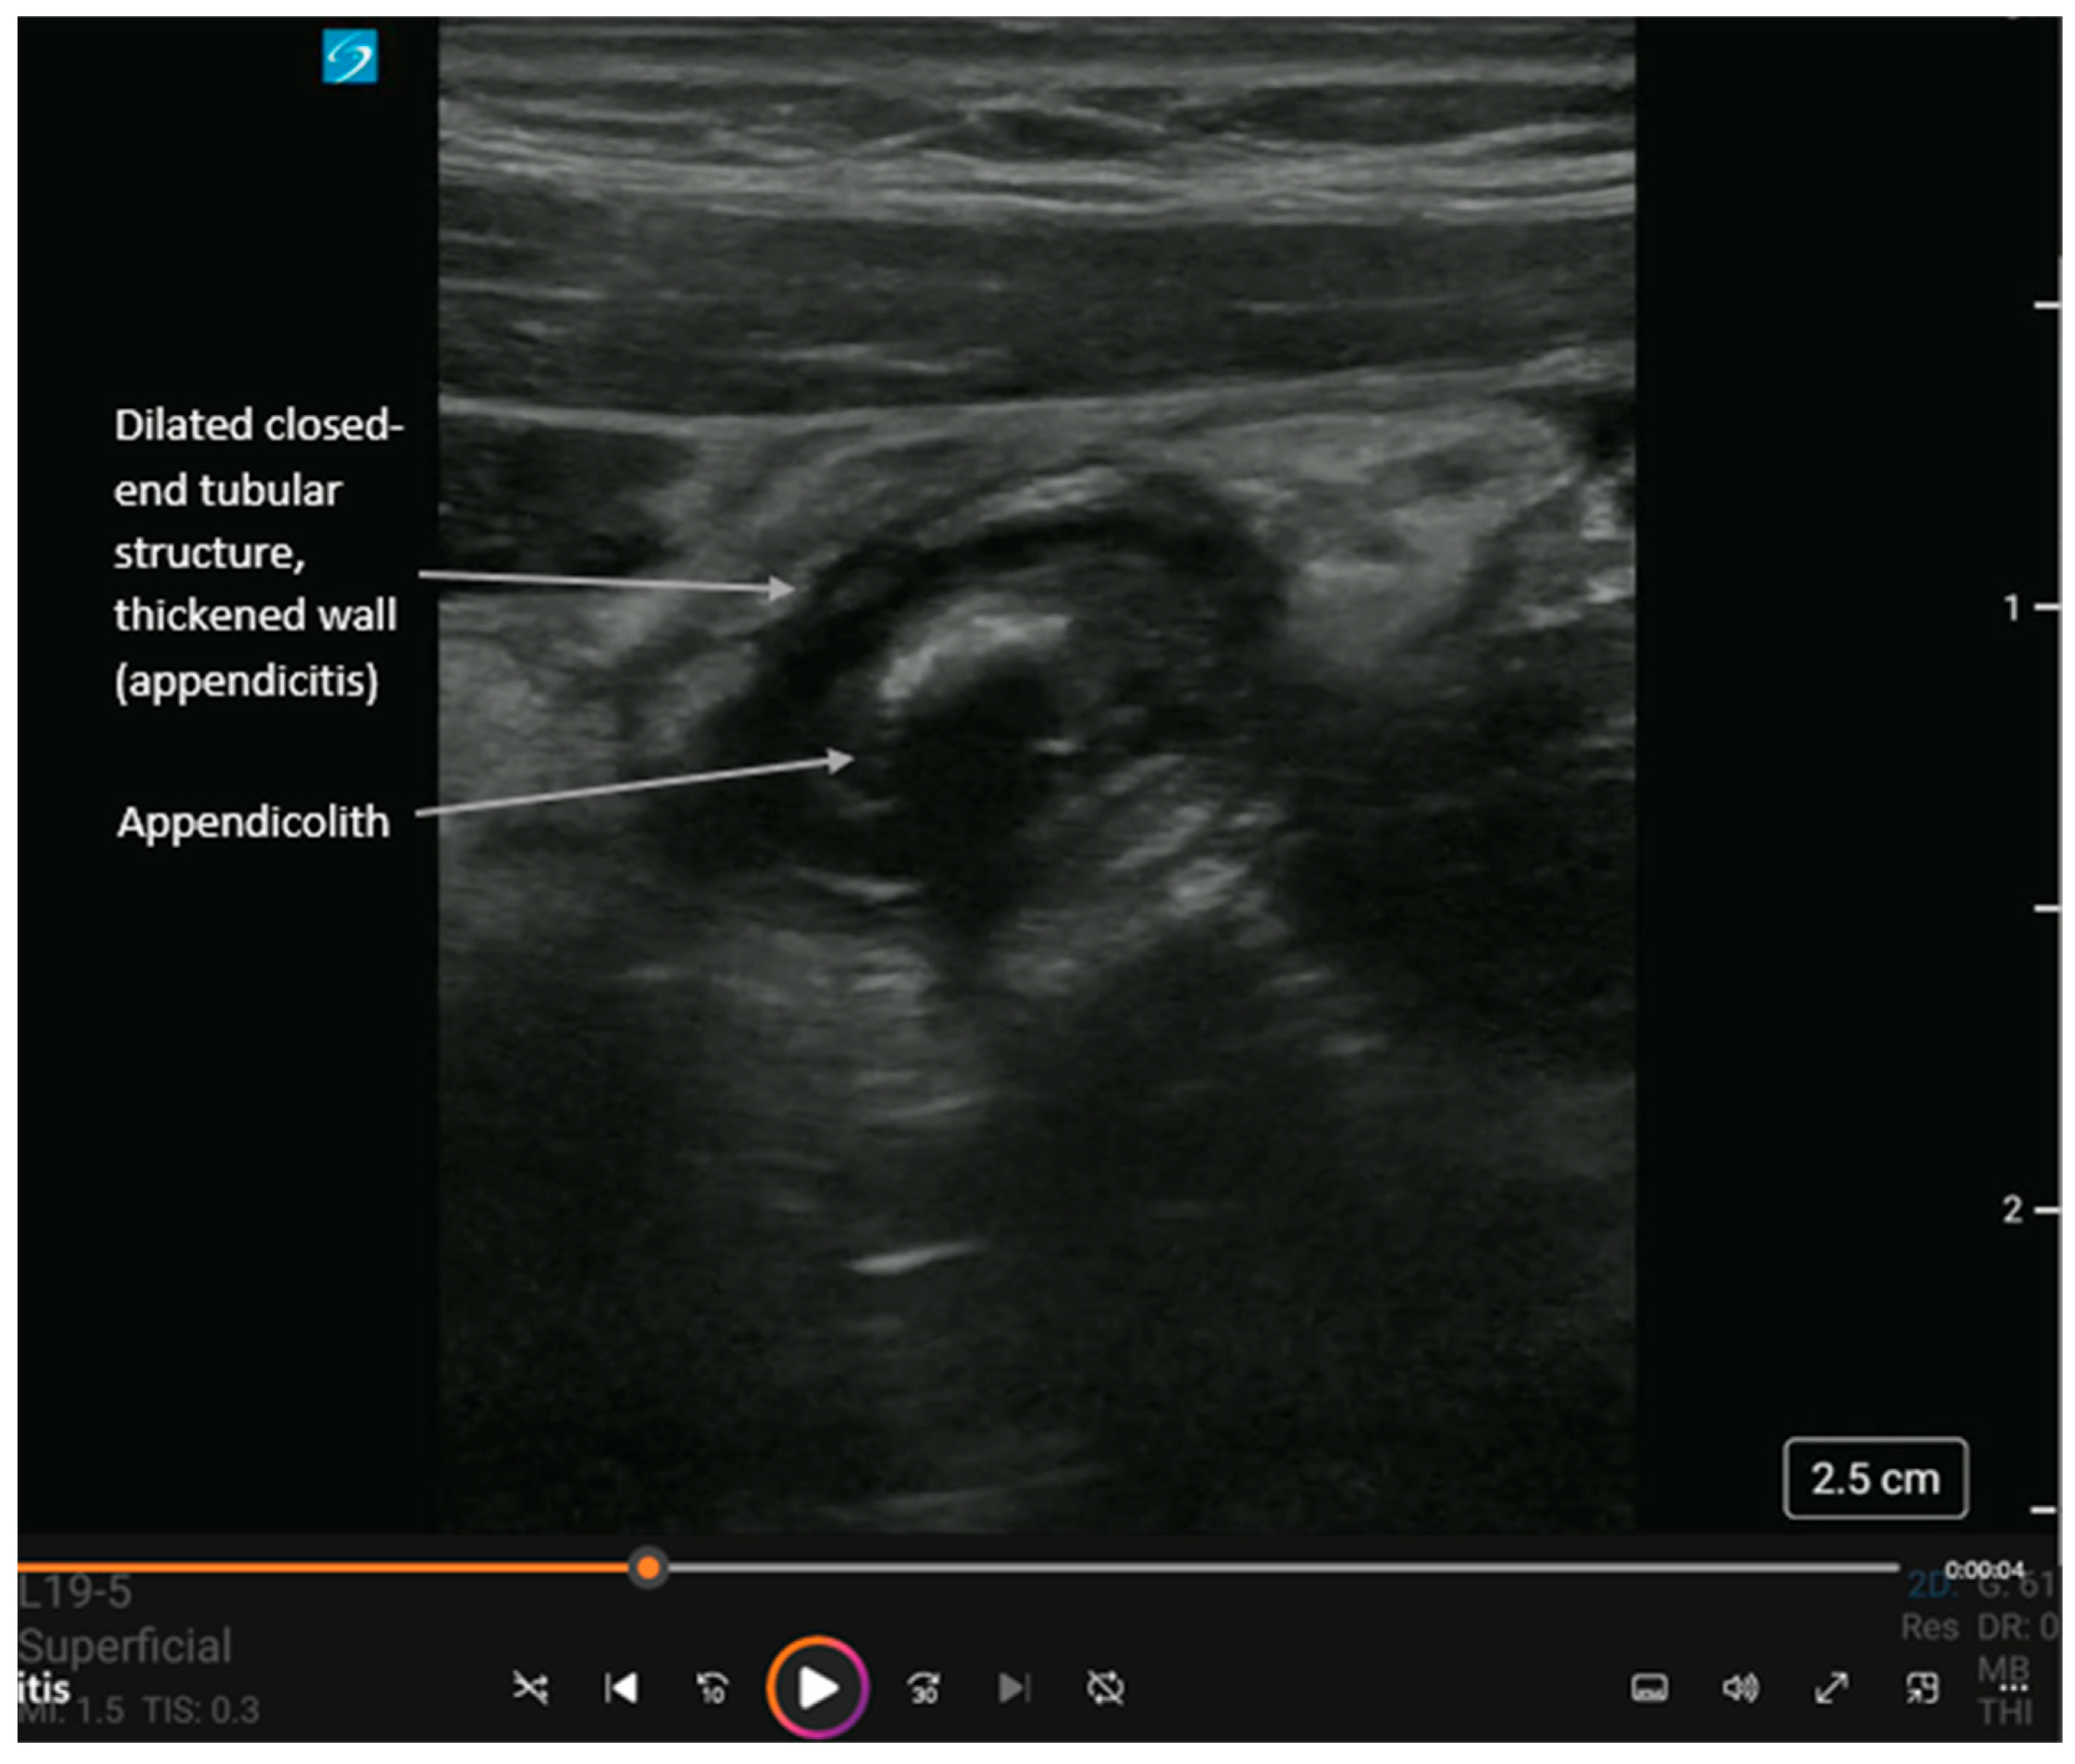

Short-axis view of acute appendicitis with an appendicolith and dynamic findings in Supplementary Video S4. The appendix is a closed-ended tubular structure usually found in the right lower quadrant of the abdomen. Landmarks for locating the appendix are the psoas muscle laterally and inferiorly, the external iliac vessels medially and inferiorly, and the internal oblique and transversus abdominis muscles anteriorly. In cases of acute appendicitis, the appendix diameter is dilated > 5 mm and non-compressible. Like with diverticulitis, ultrasound shows (i) thickened bowel wall > 3 mm, (ii) hyperemic bowel wall, and (iii) hyperechoic surrounding fat. An appendicolith (hyperechoic circular structure with posterior shadowing) or debris may be visualized within the bowel lumen. Also, complications can include extra-luminal free fluid (anechoic adjacent to the appendix), an abscess (heterogeneous collection adjacent to the appendix), or perforation (disruption of the appendiceal wall with either free fluid or abscess). While operator-dependent, recent meta-analyses report pooled sensitivity and specificity for POCUS diagnosis of appendicitis to be approximately 81% and 87%, respectively, making it a highly effective rule-in tool [19,20,21,22].